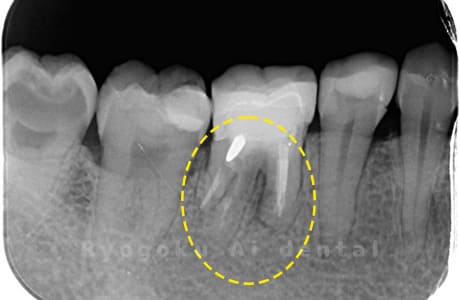

Case03

-

- 原因

- 歯牙破折

- 治療内容

- MTA治療

- 治療費用

- ¥55,000

右下の奥の歯が割れているとのことで他院で抜歯を宣告され、保存希望で当医院来院された患者様です。歯周ポケットもなくなり、現在、問題なく経過しており、患者様も満足されております。

<リスク・副作用>

手術後は痛み、腫れ、痺れ、青あざなどの副作用が生じます。痛みは痛み止めを処方しますが、腫れ、青あざは1週間程度生じる場合があります。また、部位によっては神経の走行が複雑で、痺れが残り、長期的にお薬を処方する場合があります。